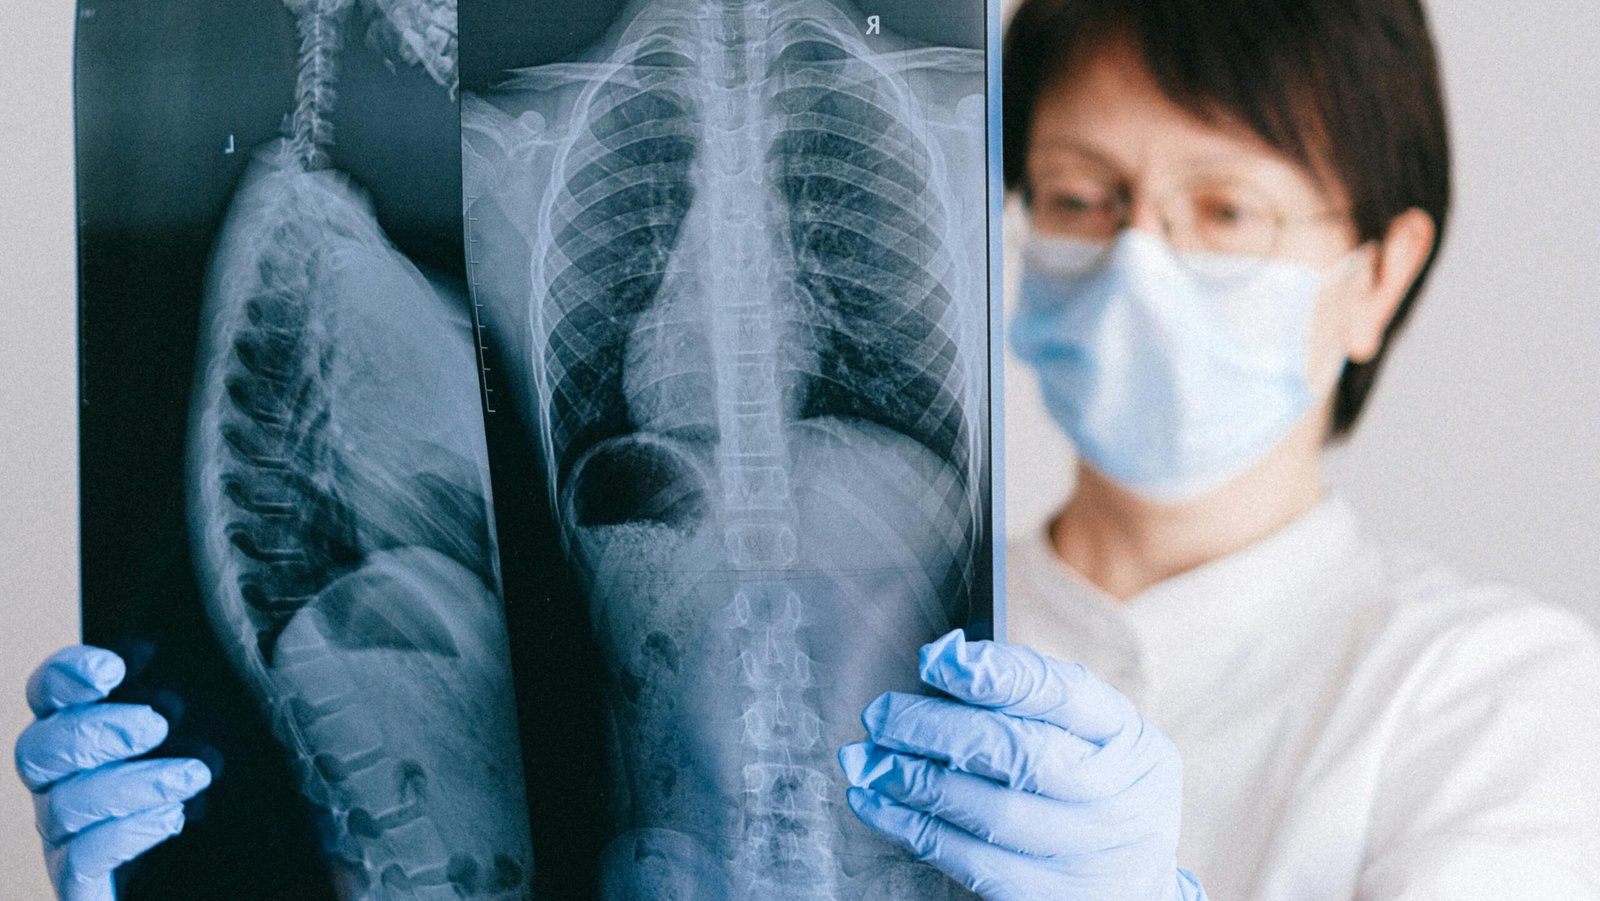

The structure of your spine consists of 33 interconnected bones which are separated through the presence of intervertebral discs that function as gel-like cushions. The discs function as tiny sponges which consist mostly of water because they exist in their fullest state of plumpness after a night of sleep.

As soon as you stand up, gravitational forces begin to exert their influence on your physical form. The downward force causes the spongy discs to experience pressure which results in gradual fluid removal through your daily activities of walking and sitting and standing.

Your spine has undergone substantial compression during several hours of standing from the time you started until 4 PM. The disc “creep response” leads to disc thinning which results in your body reaching its shortest height before you leave work.

Sleep time enables your body to release the burden which has been maintained on your spine. The horizontal position permits your discs to absorb body fluids which leads them to expand back to their original size.